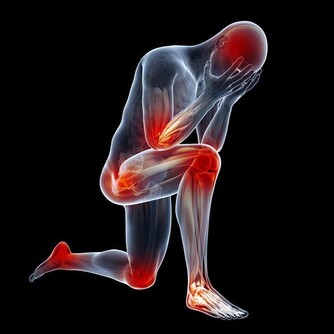

在夏天的悶熱過後,很快就迎來了秋天的涼爽與乾燥,老百姓都知道秋天是比較乾燥的季節,這個時期,對於鼻子粘膜比較薄的人會出現鼻出血的情況,對於肺臟本身不是很好的人,容易在這個時期出現咳嗽的表現,這些其實都是秋燥傷害了人體正常的陰液分佈,導致的結果。